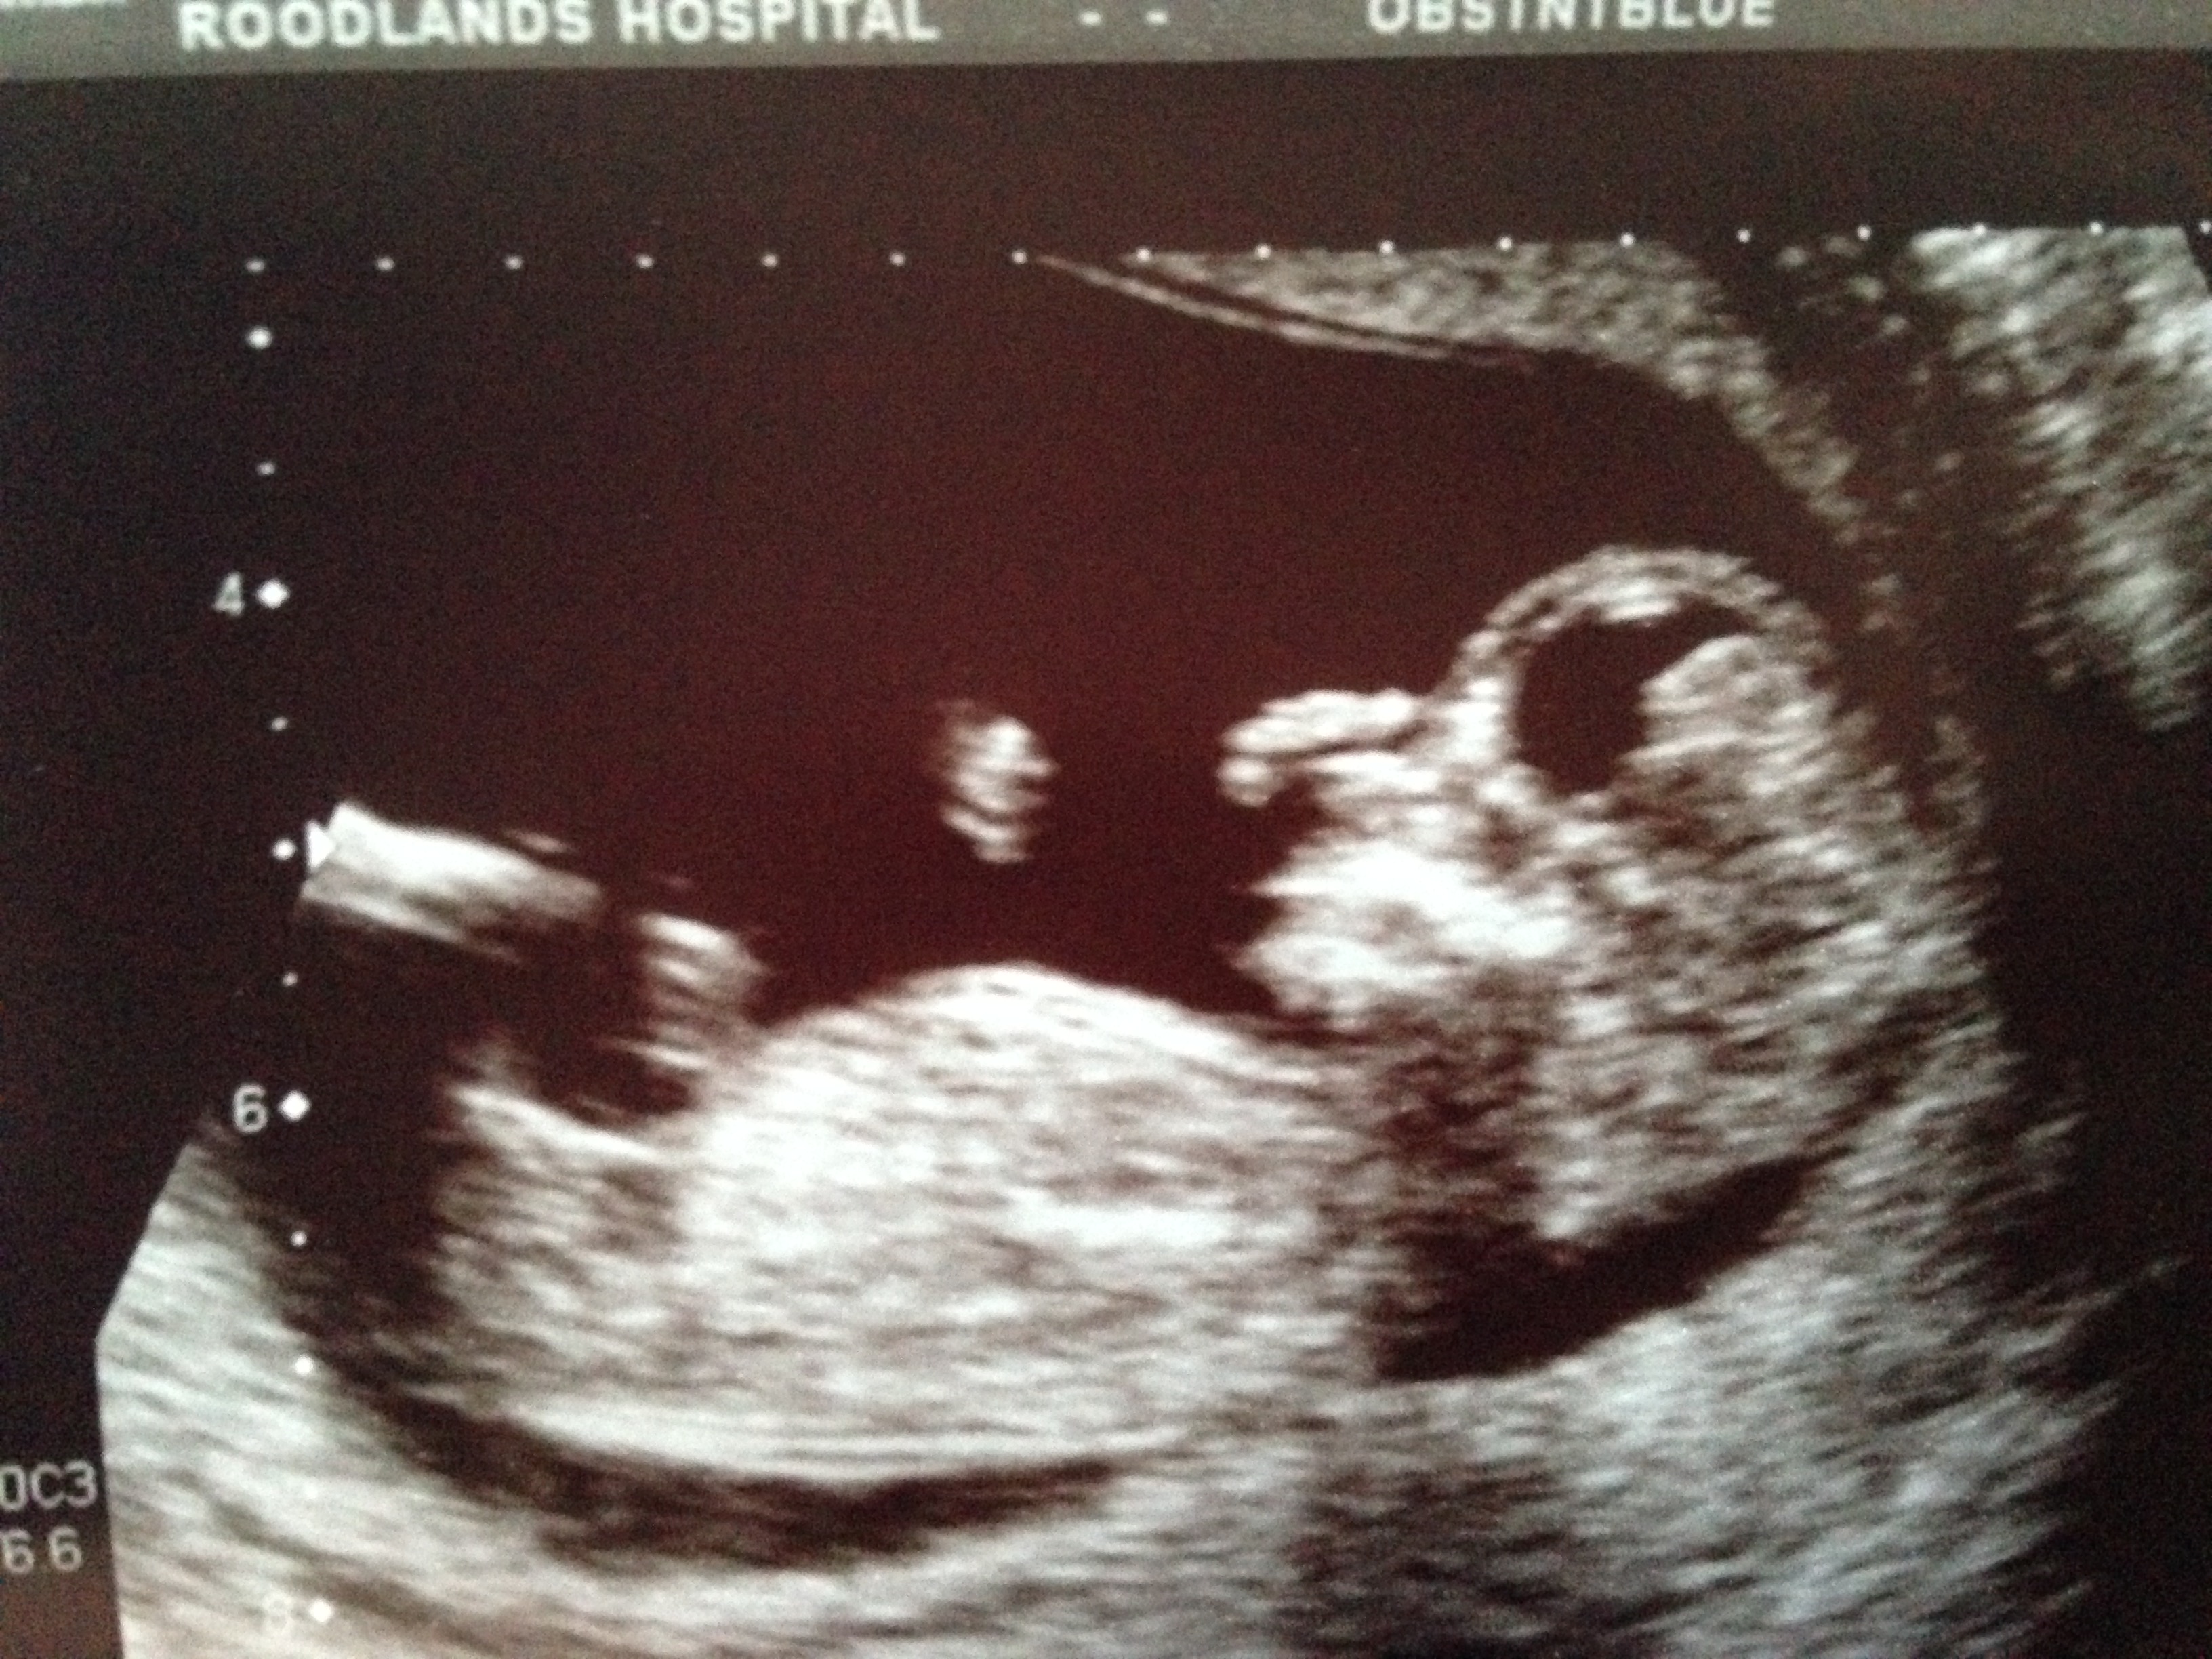

pretty please nub gusses its driving me crazy 12w 6 days

Attachment 21865

All guesses welcome.